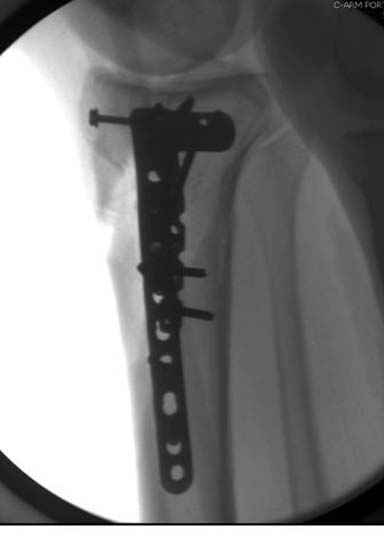

Решили выполнить остеосинтез штифтом и внутрисуставного перелома пластиной и винтами. Жду мнения! Зачем мне оправдываться-я же не преступник. Диалогом называется...

Отдельные переломы тибиал плато и перелом проксимальной трети большеберцовой кости отличаются от переломов тибиал плато с вовлечением диафиза. Здесь перелом тибиал плато типа Schatzker VI, полученный в результате высокоэнергетической травмы. Перелом метафиза образовал отрыв суставной поверхности от диафиза с вовлечением медиального и латерального мыщелков. Двухмыщелковые переломы из-за укрочения опасны развитием компартаментального синдрома, повреждением латерального мениска и связок.

При переломах одного из мыщелков тибиал плато+дополнительный перелом проксимальной трети большеберцовой кости можно применить комбинированный вариант фиксации, т.е. мыщелок винтами или пластиной, а для диафиза можно установить гвоздь. В данном варианте потеряно преимущество гвоздя , из-за серьезной травмы суставной поверхности нельзя нагружать ногу несколько месяцев. А без нагрузки гвоздь просто заполнитель пространства внутри кости!

На вашем место я бы подождал с фиксацией до готовности кожных покровов, и за это время можно было подобрать соответствующий фиксатор, т.е более длинная пластина снаружи и медиальная пластина на апексе перелома как подпорка. Здесь приемлем как раз минимальный доступ.

Имеющаяся импрессия не потребовала пластики - достаточным оказалось поднять отломок

Если там действительная импрессия, пустое место без структуральных заполнителей, кость или синтетические материалы, не восстановится, а образуется коллапс, и ось конечности поведет после нагрузки. Кроме того там возможно "болт стяжка"?, в медиальной стороне выступает за кортекс, можно было укоротить! Потом создается впечатление, что не соответствуют мыщелки большеберцовой и бедренной костей? Покажите снимок.